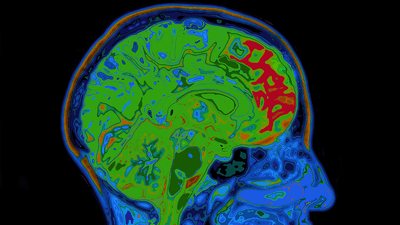

The patient was assessed and found to have difficulties with memory, verbal memory, and had a tendency to conflate two stories into one. Using cognitive tests and scans of his brain, the team found signs of Alzheimer's Disease.